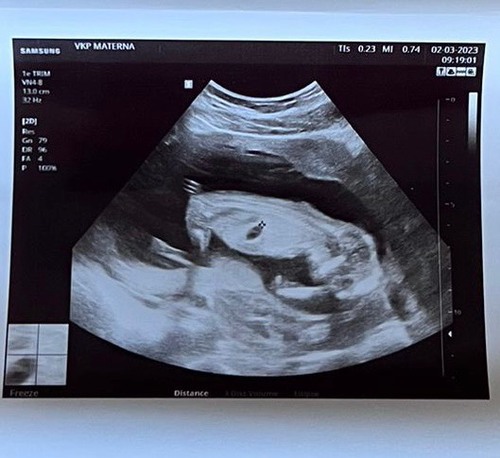

Hi allemaal! Vandaag de 13 weken echo gehad en ik ben heel benieuwd of jullie hier iets in kunnen zien? 😍

Deze is van 11 weken

Nog een tweede foto. Ik ben hier 13w en 5dagen